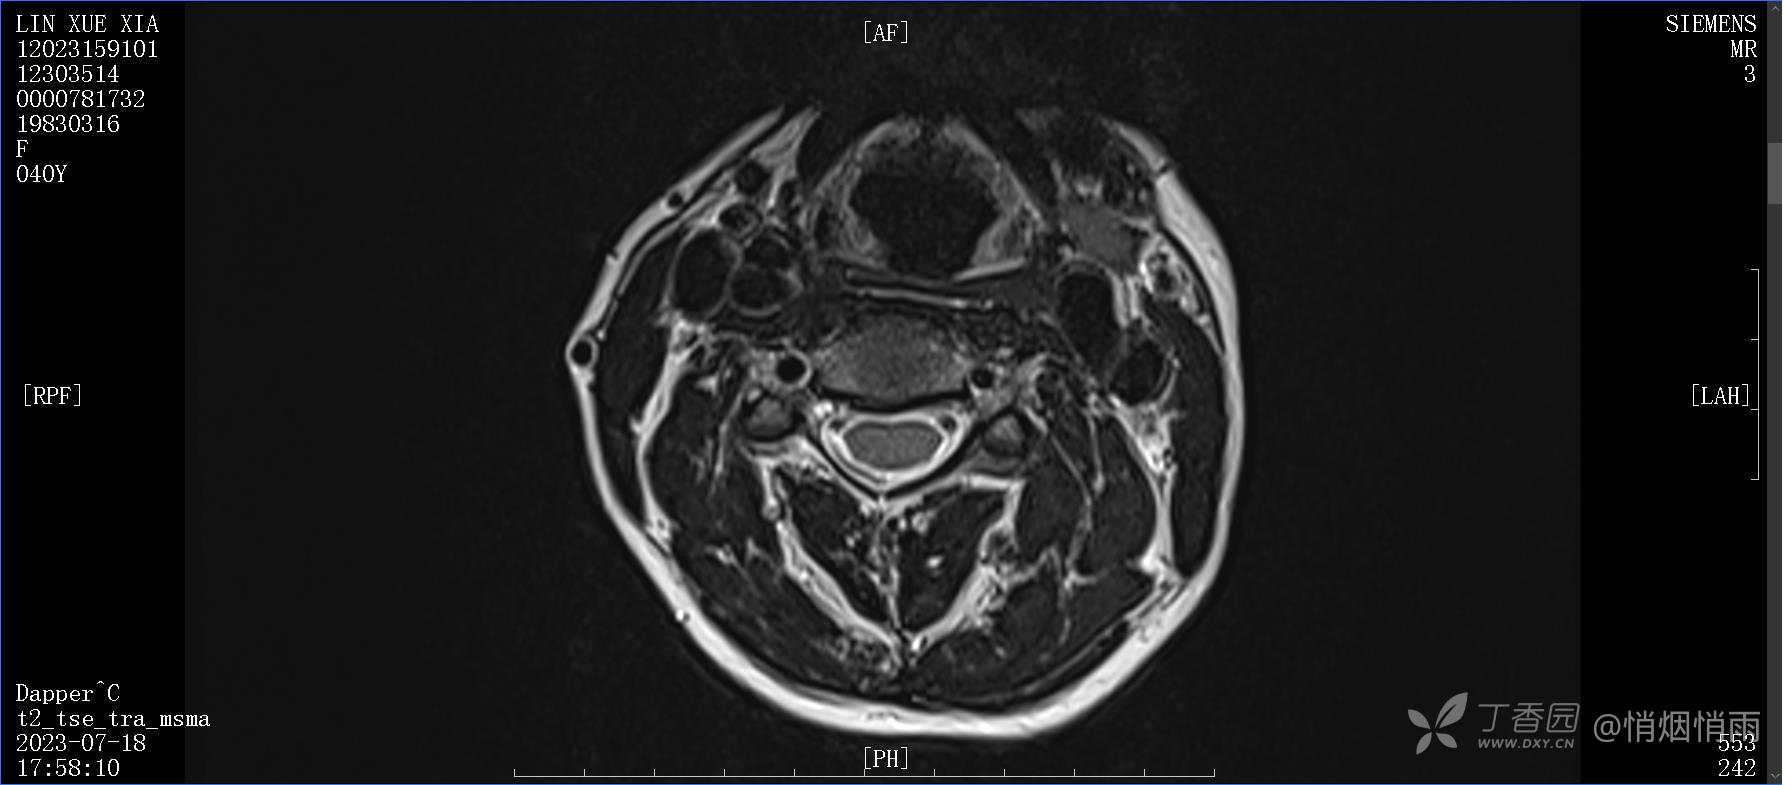

NeurothinkerZ 推荐患者女性,40岁,因右肩背部疼痛班活动受限4日余入院(2023-07-17)。

查体:右肩关节局部轻度肿胀,肩胛区压痛明显,痛处不固定,肩关节痛性活动受限,jobe test(+),lift -off test(+),中指、环指感觉较余指减退,余肢端感觉及血运情况可。

目前的诊断,暂时依据辅助检查诊为肩袖损伤,但是患者疼痛的性质和特点,却不是单纯的肩袖损伤所致。考虑过胸廓出口综合征,但是该疾病会出现肩胛区的疼痛吗?(由于考虑到费用的问题,没再进行下一步的检查)带状疱疹会有如此的症状吗?